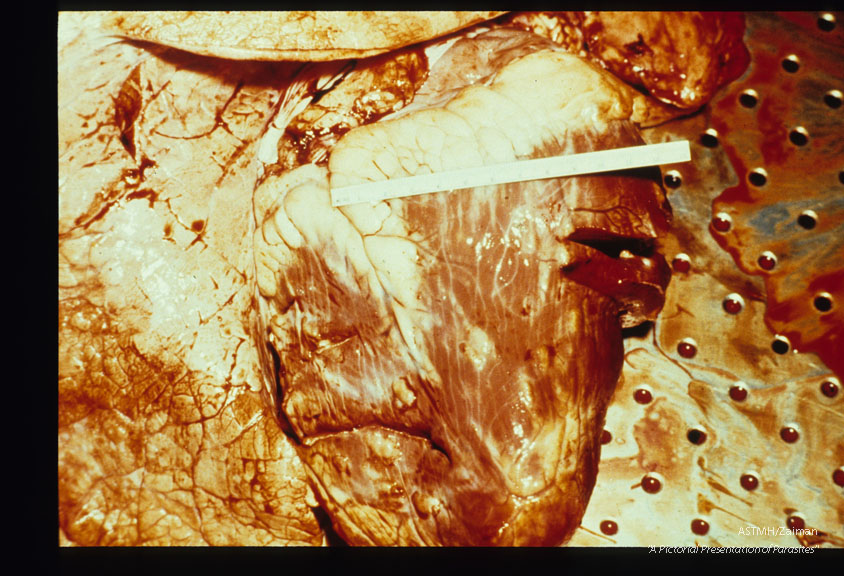

Beef heart harboring multiple cysticerci. Gross specimen.

Taenia saginata

Description: Beef heart harboring multiple cysticerci. Gross specimen.